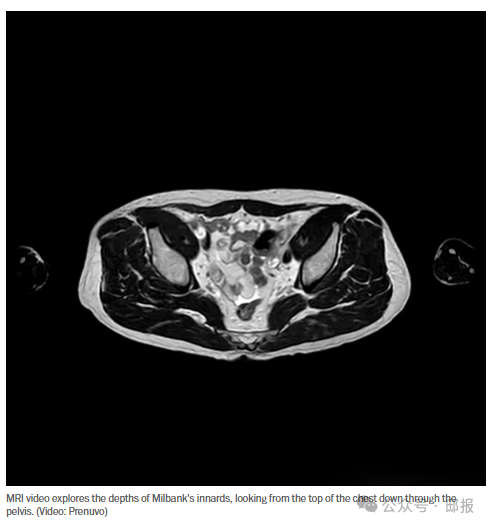

我總懷疑自己得了什麼病,於是做了全身核磁共振

所以,幾年前當我第一次聽到那些長壽專家吹捧全身核磁共振掃描時,我自然而然地就准備報名了。這可是個從大腦到跖骨檢查全身,甚至能找到小至2毫米的異常點的絕佳機會。我再也不用憑空想象自己有什麼毛病了。現在我可以安心地告訴自己我很健康——或者毫無疑問地證明自己病入膏肓。

驅動這些全身 MRI 的新技術——一種叫做擴散加權成像(別問我怎麼解釋)的技術,結合人工智能的模式識別——有可能通過在癌症初期、無症狀動脈瘤和其他隱藏的潛在殺手變得致命之前將其發現,從而拯救我們的生命。

親愛的讀者,我沒有什麼需要對您隱瞞的,所以我在這篇專欄文章中附上了我的內臓照片。其他記者或許會高談闊論透明度,但他們當中又有多少人向您展示過自己脾臓的視頻呢?